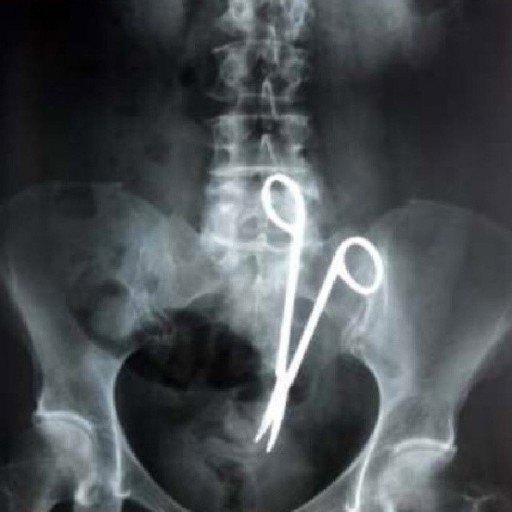

의료진은 수술 도구를 사용하여 덤벨을 제거하려 시도하였지만 불가능했다고 하며 결국 의사가 직접 손을 집어넣어 덤벨을 빼냈다고 합니다.